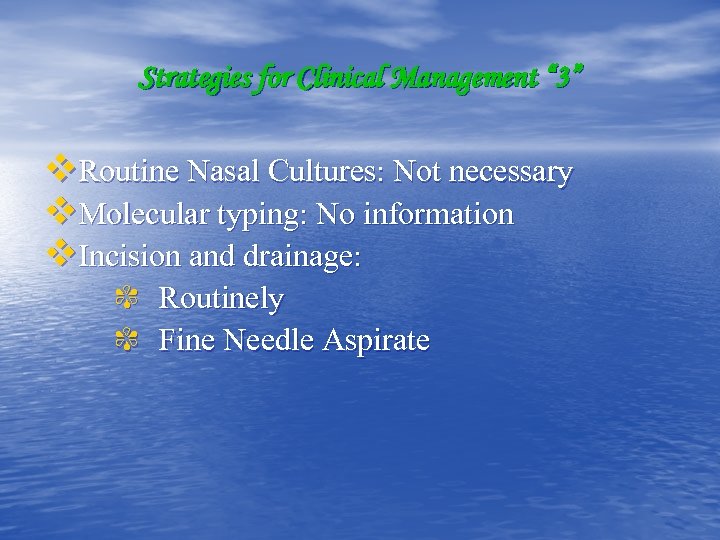

Strategies for Clinical Management “ 3” v. Routine Nasal Cultures: Not necessary v. Molecular typing: No information v. Incision and drainage: ✾ Routinely ✾ Fine Needle Aspirate

Strategies for Clinical Management “ 3” v. Routine Nasal Cultures: Not necessary v. Molecular typing: No information v. Incision and drainage: ✾ Routinely ✾ Fine Needle Aspirate